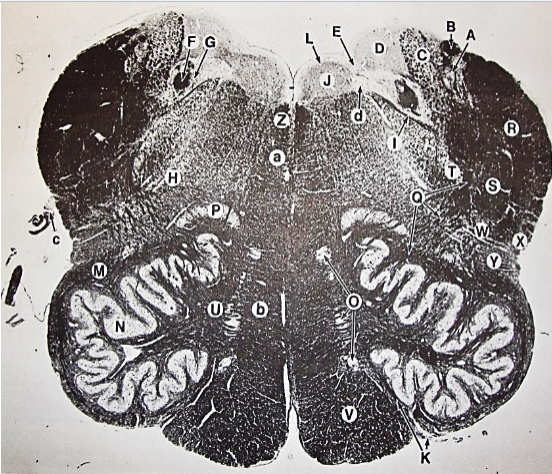

A

fasciculus gracilis

B

gracile nucleus

C

fasciculus cuneatus

D

cuneate nucleus

F

internal arcuate fibers

G

decussation of internal arcuate fibers

H

medial lemniscus

I

hypoglossal nucleus

J

dorsal motor nucleus vagus

K

solitary fasciculus

L

solitary nucleus

M

dorsal longitudinal fasciculus

N

spinal trigeminal tract

O

spinal trigeminal nucleus

P

posterior spinocerebellar tract

Q

anterior spinocerebellar tract

R

spinal lemniscus

S

lateral vestibulospinal tract

T

rubrospinal tract

U

lateral reticular nucleus

V

medial accessary olivary nucleus

W

pyramidal (corticospinal) tract

X

arcuate nucelus

Y

medial longitudinal fasciculus

Z

tectospinal tract

a

fascicles of hypoglossal nerve